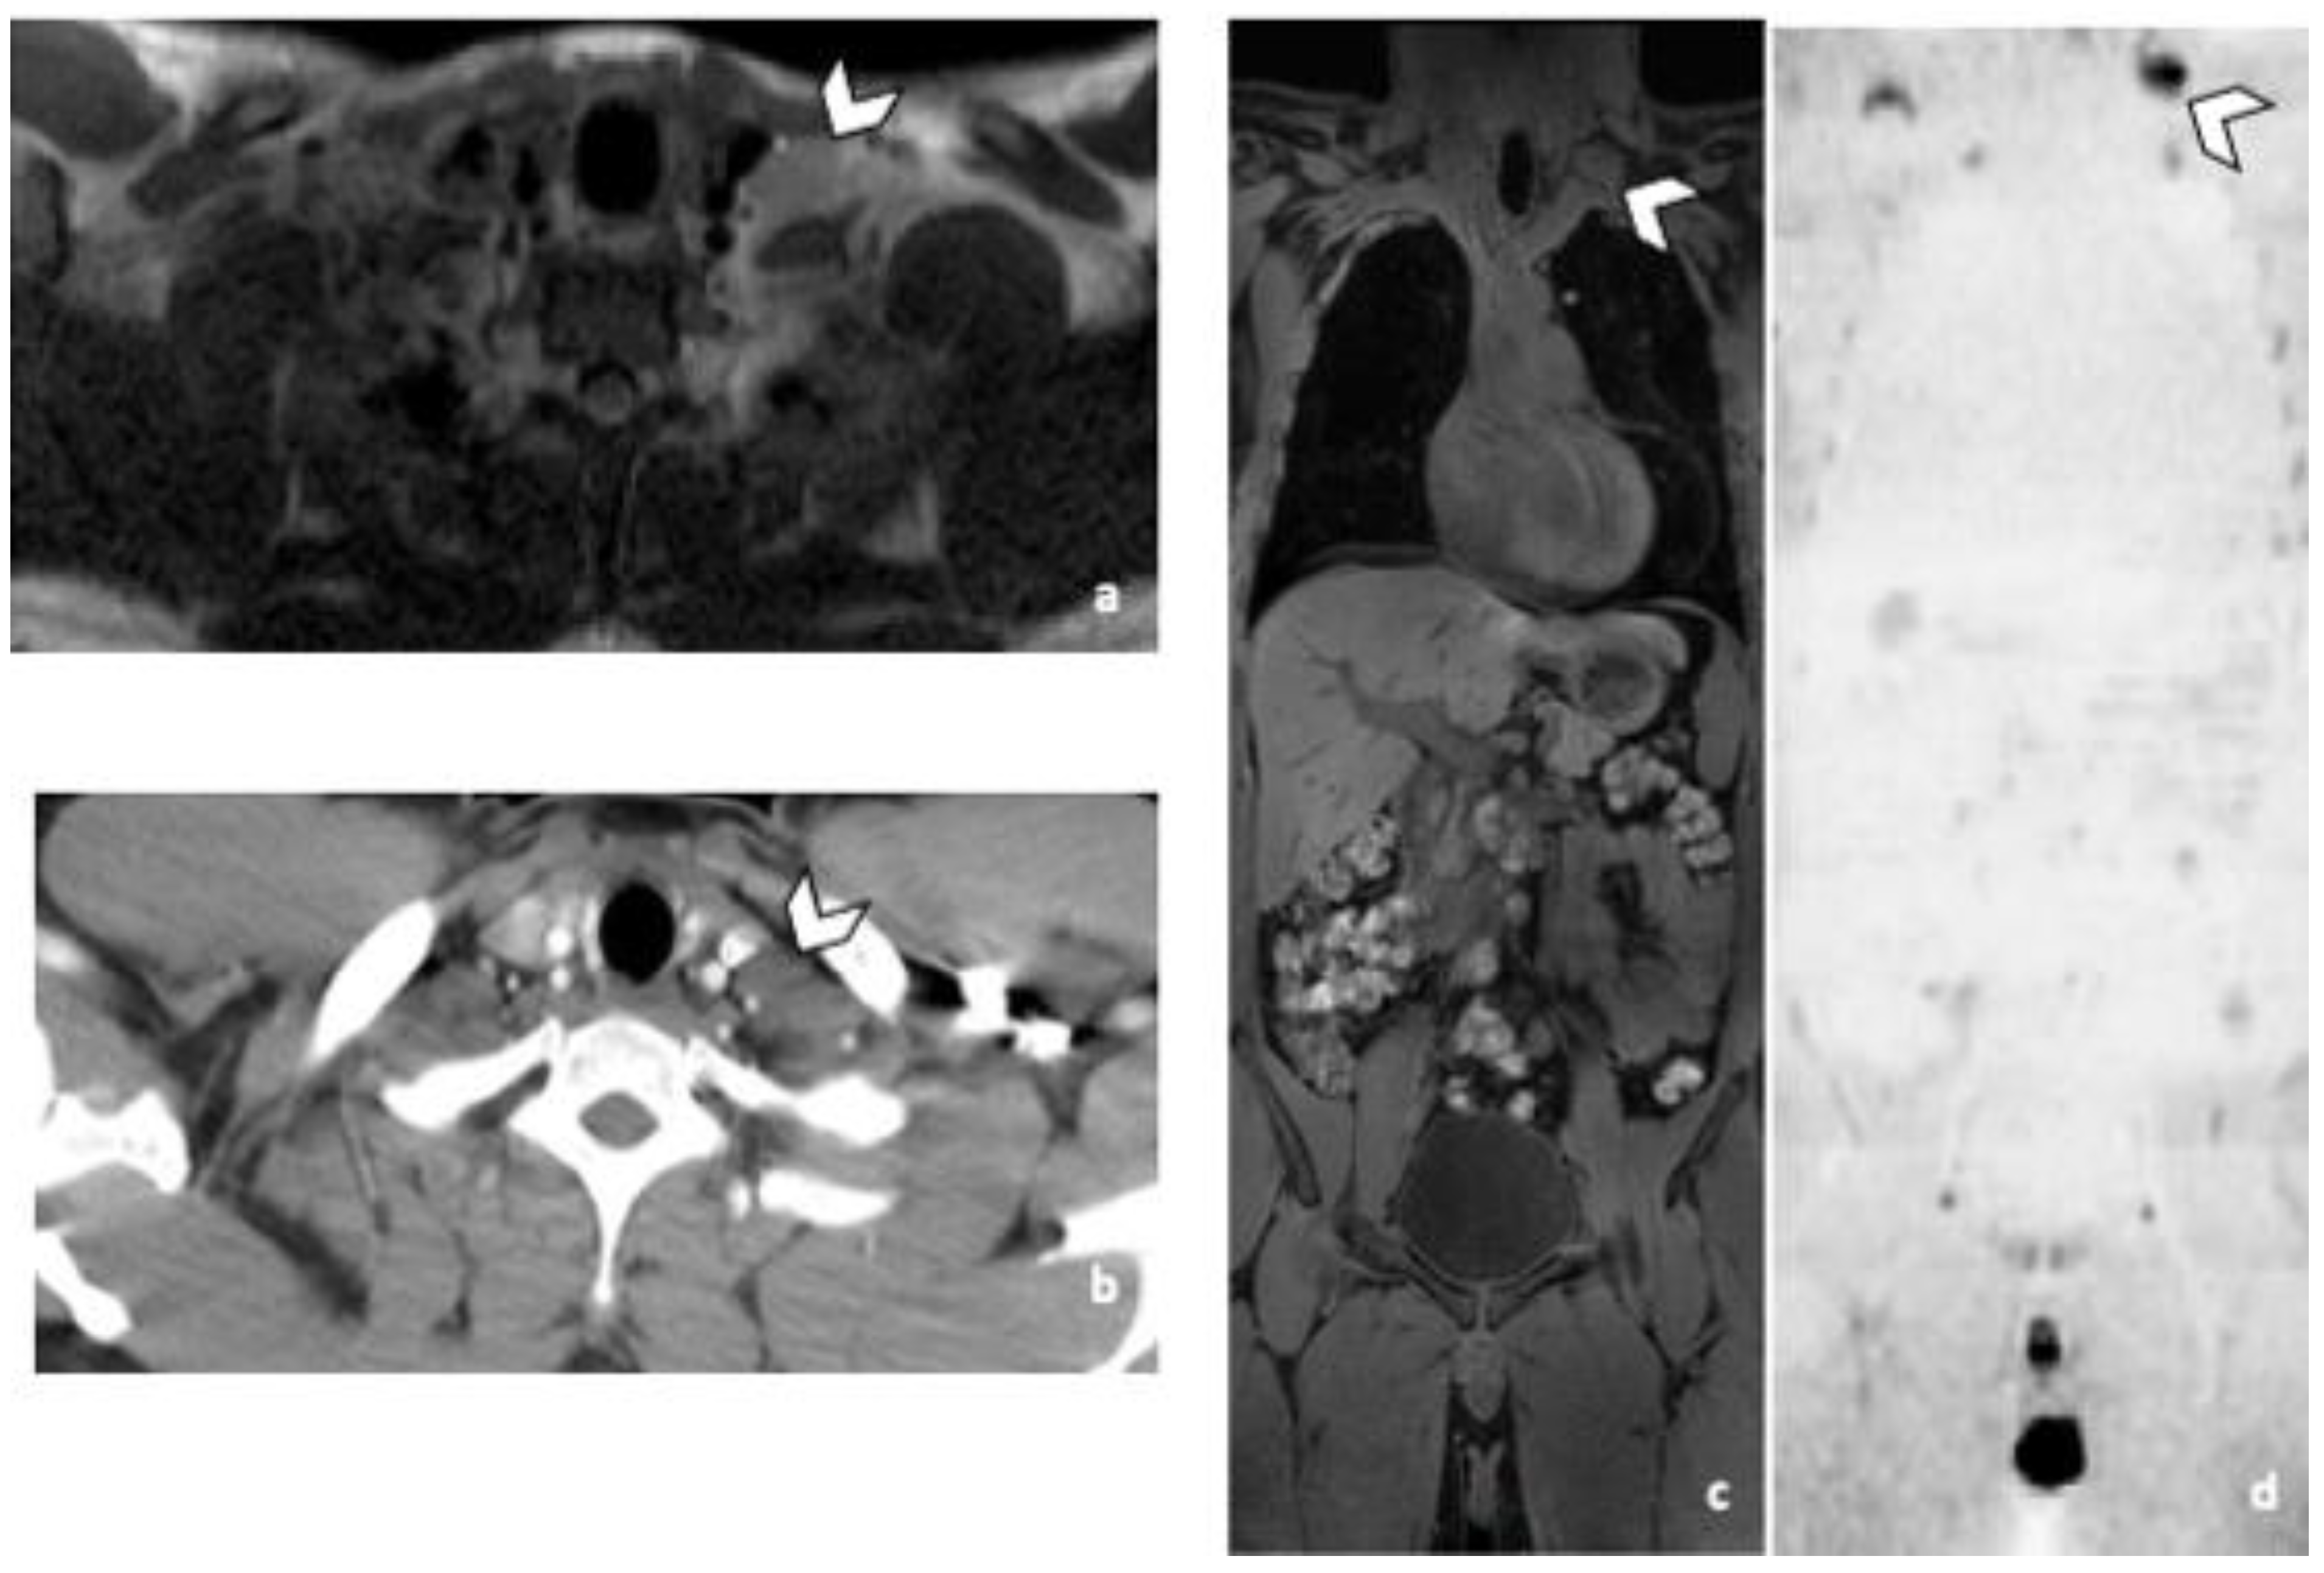

3.3.2. DLN Metastases

Predictive Accuracy of CT was 93%. Accuracy of WB-MRI was at least 98%, regardless of the imaging protocol. Only marginal variation in accuracy was observed between readers.

Practically with the sole use of CT, 2 and 3 patients with supradiaphragmatic LN would have been missed depending on the reader. R1 missed 3 supra-diaphragmatic DLN and R2 two during CT readings. Both readers missed one patient, because of the non-contrast CT due to allergy contraindication. The second patient missed by both readers, had a left supraclavicular LN in the limit of the field of view of the CT (Figure 3). Its detection was difficult because of its inherent contrast. The inherent contrast is the extent to which the attenuation coefficient value of a structure differs from the one of the surrounding tissues [16]. In this case the attenuation values of the LN and the surrounding muscles are similar, the contrast is low and the lesions are not easily distinguishable. Another reason could be the arm raised position. The third DLN patient missed by one of the two readers during the CT readings, had a paraoesophageal LN, better visualized in MRI and DWI sequence (Figure 4). For R2 the specificity of both techniques was 97% for DLN because a thymic cyst was misinterpreted as a necrotic LN.

Figure 3.

False negative supra-diaphragmatic lymph node during the CT reading in a 28-year-old man with NSGCC. Axial T2-weighted image (a), coronal reformatted 3D T1 GRE Fat Sat (c) and high b-value DWI (inverted greyscale, b = 1000 s/mm2) MR images of the whole body (d) and axial CT image after intravenous injection of iodinated contrast agent (b). The enlarged left supra-clavicular lymph node (arrowhead) was identified by both readers during the MRI readings; it was missed by both readers during the CT readings. Abbreviations: NSGCC: Non-Seminomatous Germ Cell Cancer, 3D: Three Dimensional, T1 GRE: T1 Gradient Echo, DWI: Diffusion Weighted Imaging, MRI: Magnetic Resonance Imaging, CT: Computed Tomography.

Figure 4.

Comparison of WB sequences in a 39-year-old patient with NSGCC. Axial T2-weighted (a), 3D T1 GRE In Phase (b) and high b-value DWI (b = 1000 s/mm2) MR images. One of the readers missed an enlarged paraoesophageal lymph node (arrowhead) demonstrating a high signal intensity in T2 (a), barely visible in T1 and presenting a restricted Diffusion (c). Abbreviations: NSGCC: Non-Seminomatous Germ Cell Cancer, 3D: Three Dimensional, T1 GRE: T1 Gradient Echo, DWI: Diffusion Weighted Imaging.